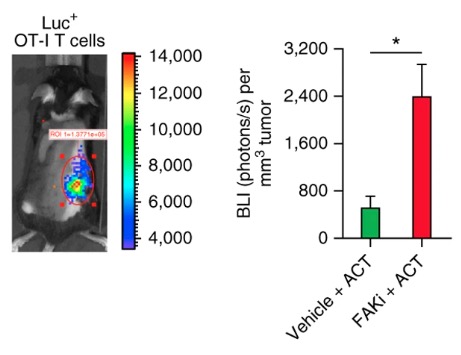

Targeting focal adhesion kinase renders pancreatic cancers responsive to checkpoint immunotherapy

doi:10.1038/nm.4123